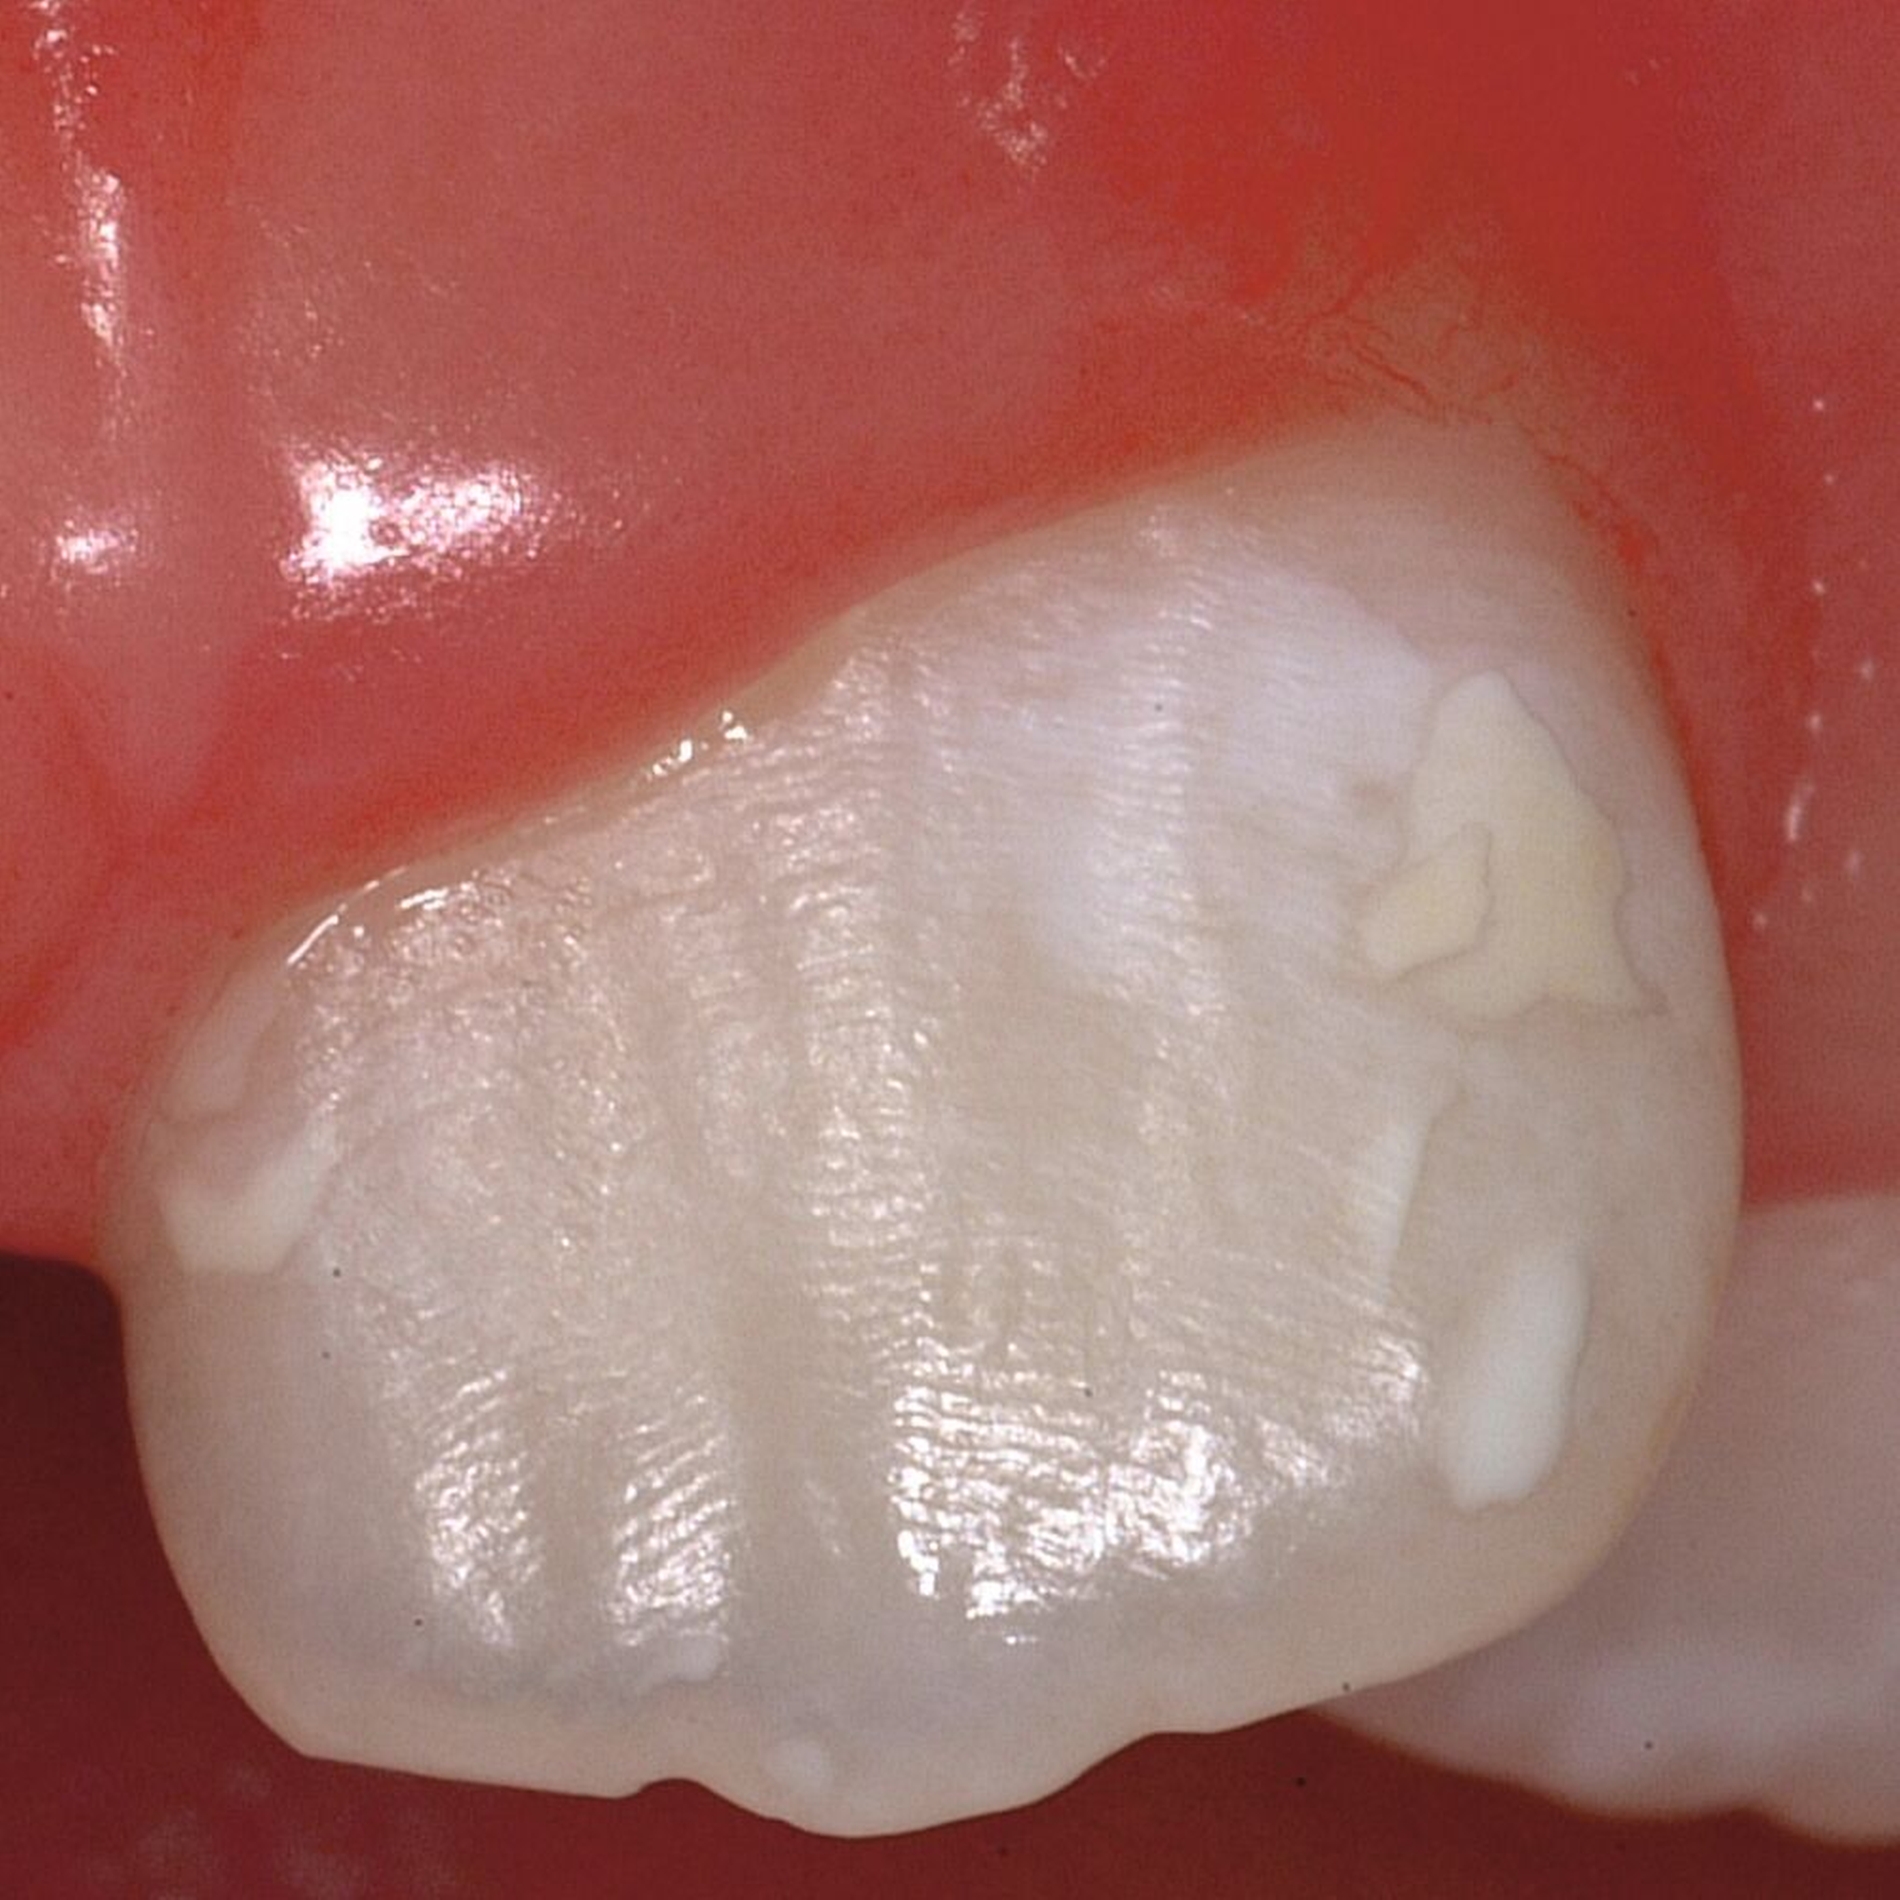

Das klinische Erscheinungsbild an bleibenden Zähnen zeigt typischerweise weißlich-gelbe bis gelblich-braune Opazitäten, die zumindest in einigen Bereichen durch eine scharfe Abgrenzung (engl.:„demarcated opacities“) zum gesunden Zahnschmelz charakterisiert sind (Abbildungen 3 und 4). Die abgegrenzten Hypomineralisationen befinden sich mehrheitlich im Bereich der inzisalen Kronenhälfte unabhängig von dem Auftreten an Front- oder Seitenzähnen. Die Ausprägung am Zahn kann dabei auf einzelne Areale oder Höcker begrenzt sein.

Für die Dokumentation und Klassifikation der MIH wurden verschiedene Systeme vorgeschlagen. Als historisch und veraltet gilt der (modifizierte) DDE-Index. Demgegenüber haben die Kriterien der EAPD – abgegrenzte Opazitäten (Abbildung 3 und 4), Schmelzeinbrüche (Abbildung 5), atypische Restaurationen (Abbildung 6) – mittlerweile die weiteste Verbreitung gefunden. Diese wurden 2003 erstmals zur Beschreibung der MIH auf empirischer Basis publiziert [Weerheijm et al., 2003] und den Jahren 2010 und 2022 im Rahmen der damaligen MIH-Workshops bestätigt [Lygidakis et al., 2010; 2022].